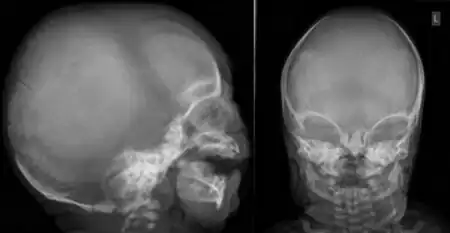

| Face shows low-set crumpled ears, and the hands showed flexion contractures of interphalangeal joints with short broad metacarpals and broad terminal phalanges with overlapping of fingers | |

The conditions are characterised by skeletal abnormalities, cleft palate (a hole in the roof of the mouth), and hearing loss.[1] These symptoms are common to craniofacial syndromes as a whole.[3] Hand defects are particularly associated.[2] Of the conditions, OPD1 has the milder phenotype, with normal intelligence and modestly reduced stature.[2] In OPD2, the characteristic facial features are more severe and intellectual disability frequent; most OPD2 cases in males are stillborn or die during infancy.[1][2] As an X-linked recessive disorder, both forms are generally more severe in males, who have one X chromosome, than females, who have two.[4] Reports from patients of their experiences demonstrate a broad spectrum of symptom severity, including within families,[5] which has also been reported in the medical literature.[6]